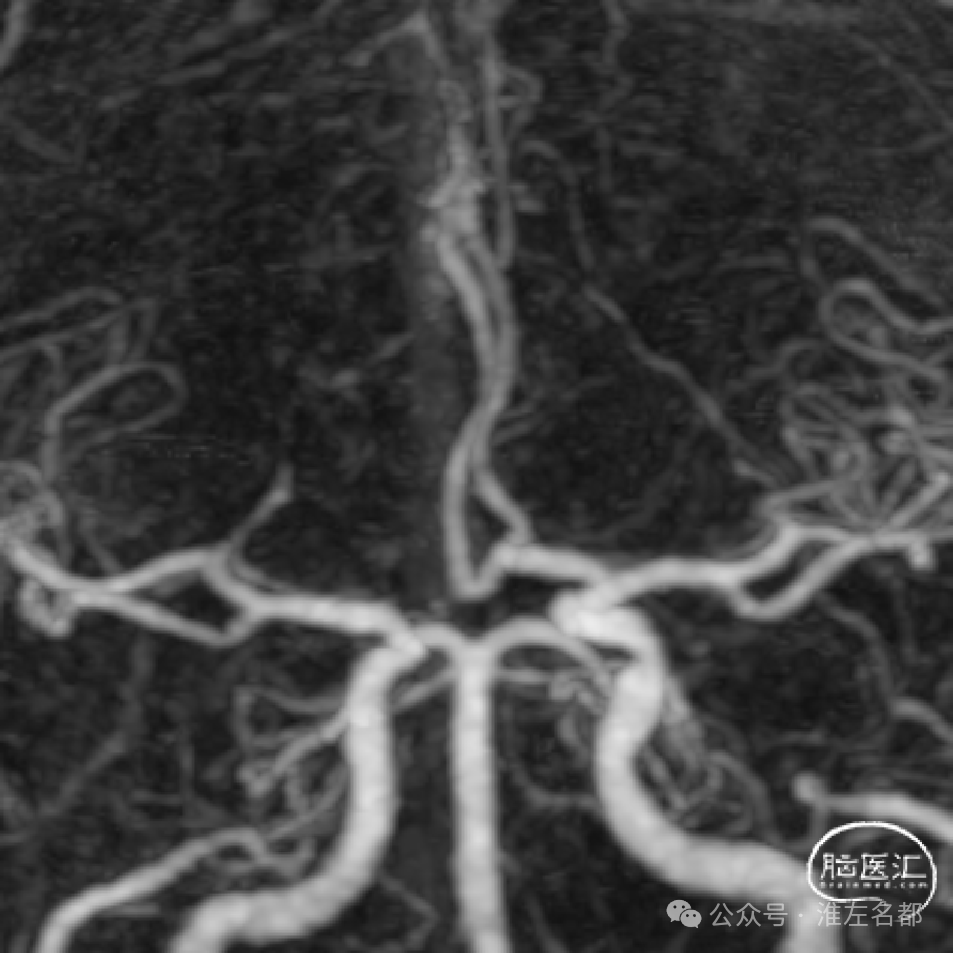

颅脑CTA:右侧大脑前动脉A2段局部管腔严重狭窄,右侧大脑前动脉A1段未发育,左侧大脑前动脉A1段粗大。

CTA:右侧大脑前动脉A2局部管腔轻微狭窄。

3D-TOF-MRA:右侧大脑前动脉A2段管腔未见明确异常。